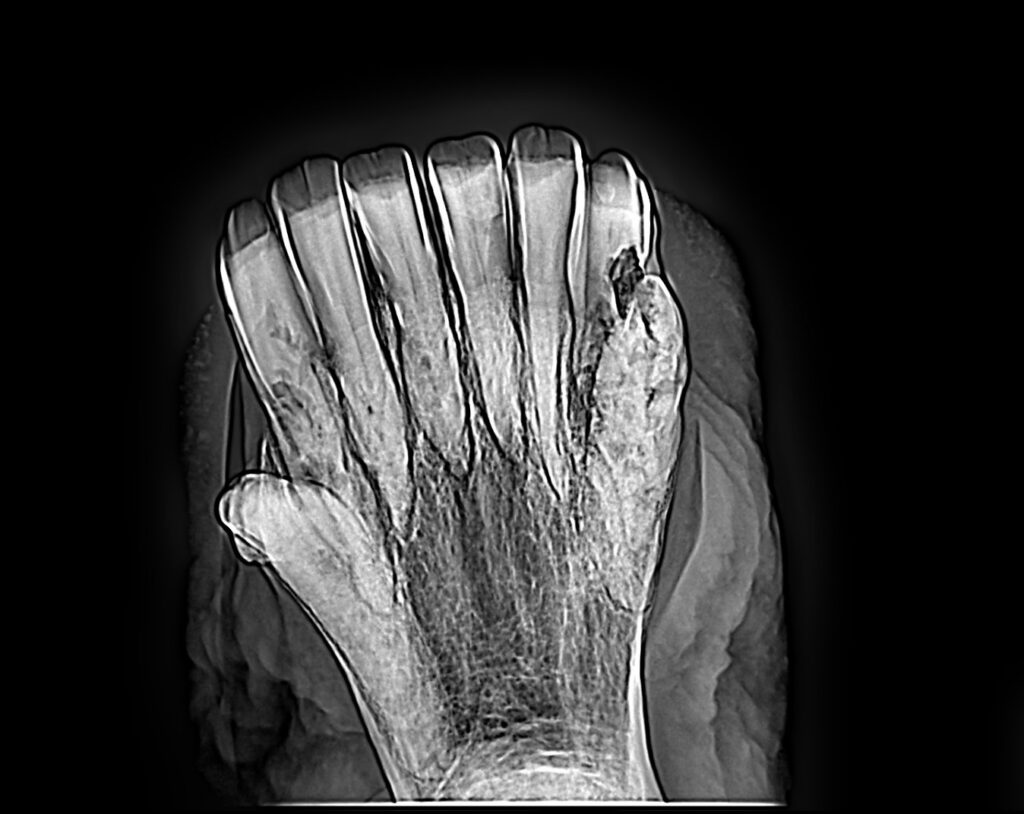

“In early cases, the teeth actually look normal and the gums look normal, but if you X-ray them, you can see that there’s some resorptive lesions there in the roots or the buried part of the tooth in the bone,” said Easley.

“Over time, they start to develop gingivitis and gum irritation,” he continued. “The affected part of the tooth that was below the gum starts showing in the mouth as the tooth continues to erupt. So, we have these black, rotten teeth that start to erupt up out of the gum, or the tooth breaks. It does become clinically apparent that something’s wrong with the teeth, and quite often it’s quite advanced by the time that happens because it’s been going on for a while.”

EOTRH is diagnosed by X-ray. This can’t be diagnosed without an X-ray, said Easley. “You can look at the horse and tell he’s got bad incisors, but you don’t know whether that’s from trauma, or malocclusion, or pockets between its teeth. You don’t know what’s causing it until you get an X-ray, and then you can see these resorptive lesions on an X-ray. They look like rats have been chewing on them; sort of moth-eaten.”